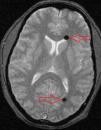

CT and MR images revealed 2 round shapes, located in the anterior and posterior areas of the left lateral ventricle, which were compatible with air bubbles (Figs. 1 and 2). MRI angiography of the intracranial vessels ruled out aneurysms, arteriovenous malformations, vertebral or internal carotid artery dissection, and venous sinus thrombosis. Our patient was diagnosed with thunderclap headache due to pneumocephalus secondary to an epidural block using the LORA technique. She received conservative treatment with analgesics and rest; symptoms resolved in a few days.